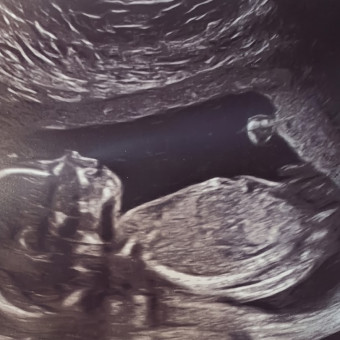

Hello! This is the second baby in our little family and it's a girl! Help us shower her with the love and care she'll need to survive her crazy brother!